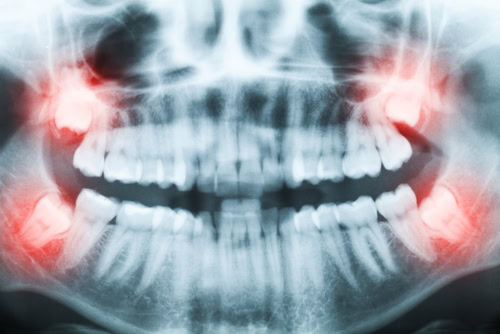

In dentistry, preserving the natural tooth is always the priority. However, there are instances where a tooth is so damaged or infected that the most effective solution is extraction. Commonly known as “pulling” a tooth, this process involves removing the tooth entirely from its socket. This creates a space that an implant-supported crown or dental bridge can fill. Wisdom tooth extraction is particularly common, as they often create spacing issues as they develop. Studies estimate that about 50% of adults have had this procedure by age 25, and 70% by age 60.

The process begins with a consultation, where Dr. Clayton will examine your teeth and take digital X-rays. Once we determine the best course of action, we’ll discuss financial options and provide pre-procedure guidelines.

No, not everyone will need their wisdom teeth removed. Even though some consider it a rite of passage, you only need your wisdom teeth extracted if their emergence will cause complications. Taking digital X-rays will help Dr. Clayton determine which teeth, if any, need to be removed.